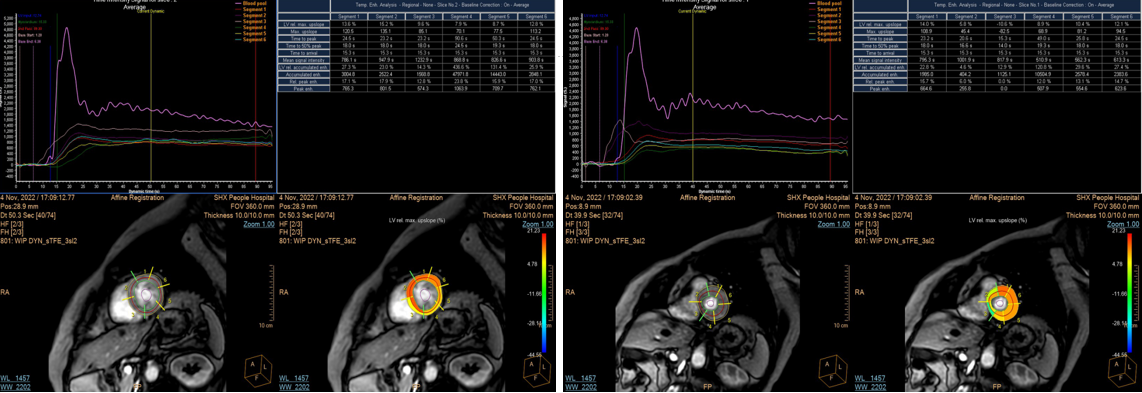

MRI负荷心肌灌注检查增加了心肌微循环障碍患者的检出率,同时通过后处理软件对微循环障碍可进行定量及半定量分析(图2)。因此负荷心肌灌注可应用于冠状动脉交界性狭窄患者、冠状动脉狭窄<50%的患者以及非缺血性心肌病患者,评估其是否存在微循环障碍,是目前检出心肌微循环障碍的可靠且无创的检查方法,为心内科医生对这类患者采取个性化治疗方案提供客观依据,并可进行疗效评价。

图2